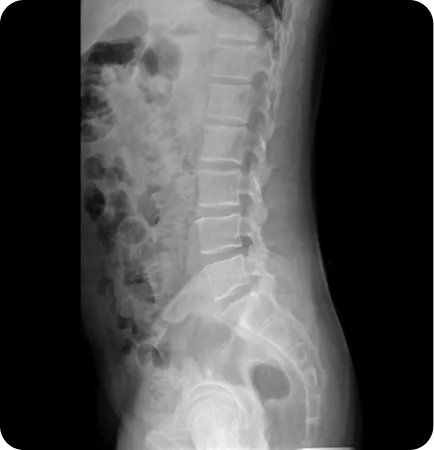

Before & After

해당 사진은 수정없는 실제 치료사진입니다.

환자의 치료결과는 환자의 상태, 치료방법 등에 따라 차이가 발생할 수 있습니다.